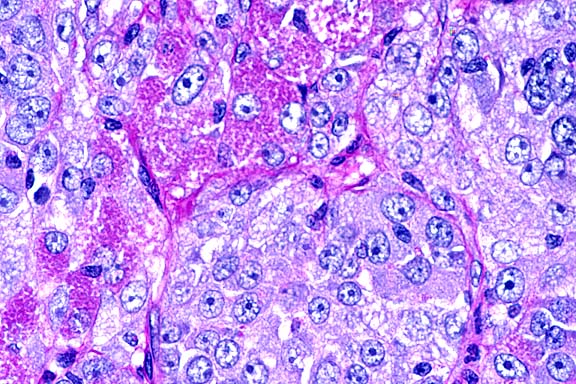

- Histologically, neoplastic tissue replaced most of the testis,

of some sections. The neoplastic cells were organized into tightly

packed sheets and large lobules divided by very fine fibrovascular

trabeculae with variably sized, scattered foci of necrosis that

often coalesced. Cells were large, and round to polygonal with

a round, normochromatic to hyperchromatic nucleus positioned

centrally or often eccentrically within a moderate amount of

eosinophilic, slightly granular cytoplasm. There was moderate

anisocytosis and anisokaryosis, and mitotic figures (which were

frequently bizarre) varied from 1 to 5 per high power field.

In many sections, clusters of neoplastic cells were seen within

peripheral blood or lymphatic vessels. Periodic acid-Schiff (PAS)

stains for glycogen revealed that most cells were negative with

slight patchy staining around the periphery of the nucleus in

some cells. Electron microscopy showed that the cells were very

undifferentiated and were not consistent with Sertoli cells or

Leydig cells, but contained some features of very early germ

cell differentiation. Immunohistochemistry revealed that the

cells were strongly positive for vimentin and S-100, but negative

for cytokeratins, neuron-specific enolase, placental alkaline

phosphatase and alpha fetoprotein.

- Case 13-2. Testis. Packeted polygonal tumor cells

rarely contain globular PAS positive cytoplasmic material.

- This case was reviewed by the Department of Genitourinary

Pathology. They interpreted the neoplasm as of Leydig cell origin,

based primarily on the characteristic cells described above.

In humans, seminomas and interstitial (Leydig) cell tumors are

distinguished primarily based on histomorphology. Additionally,

human seminomas often contain glycogen and are frequently immunopositive

for placental alkaline phosphatase. In immunohistochemical studies

conducted at the AFIP, this tumor was negative for placental

alkaline phosphatase, and most cells were PAS-negative.

- An electron micrograph of this neoplasm published in a report

of this case shows ultrastructural features of steroid producing

cells, such as interstitial (Leydig) cells, including abundant

smooth endoplasmic reticulum, presence of a Golgi complex, lamellar

and tubular mitochondrial cristae, and intracytoplasmic lipid.

No feature diagnostic of seminoma is evident.